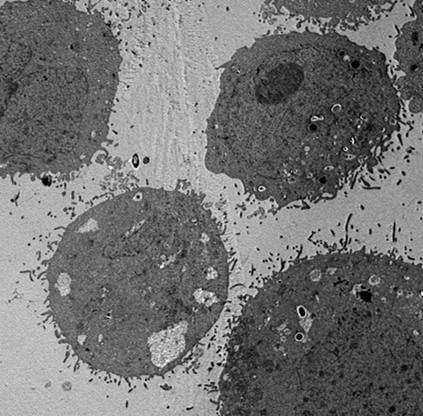

树突状细胞图片

这是我做电镜看到的细胞,我培养的是DC2.4 哪位同仁有培养DC的经验,帮我鉴定下。个人觉得突触还是挺多的,但我做流式分析表面CD80/CD86,MHCII等并没有表达,已用LPS刺激了。 求帮助,感谢!由于本人金币不多,请原谅! 1.jpg 2.jpg |